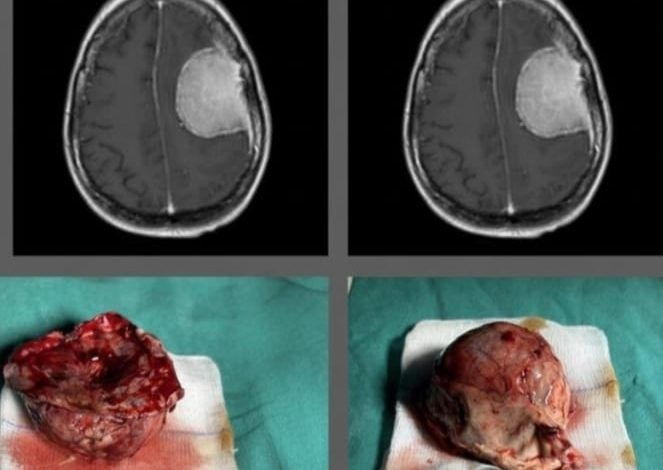

सिद्धार्थनगर। जनपद मुख्यालय न्यूरो चिकित्सा क्षेत्र में विकास का नया खाका खींच रहा है। अब न्यूरो सर्जन डा0 आशुतोष शुक्ला चिकित्सा क्षेत्र में मील का पत्थर बनकर सामने आये हैं। इन्होंने एक न्यूरो मरीज के ब्रेन से कैनवस बाल के आकार के ट्यूमर का सफल सर्जरी किया और 36 घन्टें के अन्दर मरीज को अपने पैरो पर खड़ा कर दिया। युवा डाक्टर के इस कारनामें से अब जिले के न्यूरो मरीजों को भारी राहत मिलेगी और उन्हें गैर जनपदों में जाकर इलाज कराने से छुटकारा मिलेगा। आपको बता दें कि डा0 आशुतोष ने एक महिला मरीज के मस्तिष्क ट्यूमर (ब्रेन ट्यूमर) का सफल आपरेशन कर जनपद और आस-पास के जिलों सहित पड़ोसी देश के तमाम मरीजों के लिए आशा की रोशनी जलाई है। मरीज झटकों और शरीर के दाहिने हिस्से की कमजोरी की शिकायत के साथ डॉ0 आशुतोष से मिला था। चिकित्सकीय जांचों में पाया गया कि मरीज को मैनेनजिओमा नाम का ब्रेन ट्यूमर है, जो दिमाग के एक हिस्से को प्रभावित कर रहा है और दबाव बना रहा है। ट्यूमर का आकार एक कैनवस की गेंद के बराबर बड़ा था।

सफल आपरेशन द्वारा इस ट्यूमर को डा0 आशुतोष और उनकी टीम द्वारा सर्जरी करके निकाला गया। मरीज के परिजनों ने बताया कि इस पूरी प्रक्रिया में सबसे प्रमुख और संतोष जनक बात यह रही कि ठीक 24 से 36 घन्टें बाद मरीज अपने पैरों पर चल रहा था और मात्र चार दिनों में अस्पताल से डिस्चार्ज होकर अपने घर आ गया। डॉ0 आशुतोष से हुई बात में उन्होंने बताया कि ब्रेन और स्पाइन न्यूरो सर्जरी के क्षेत्र में समाज की सेवा करने में उन्हें बहुत ही संतोष का अनुभव हो रहा है और वो इस कार्य को और भी आगे ले जाने का प्रयास करेंगे।